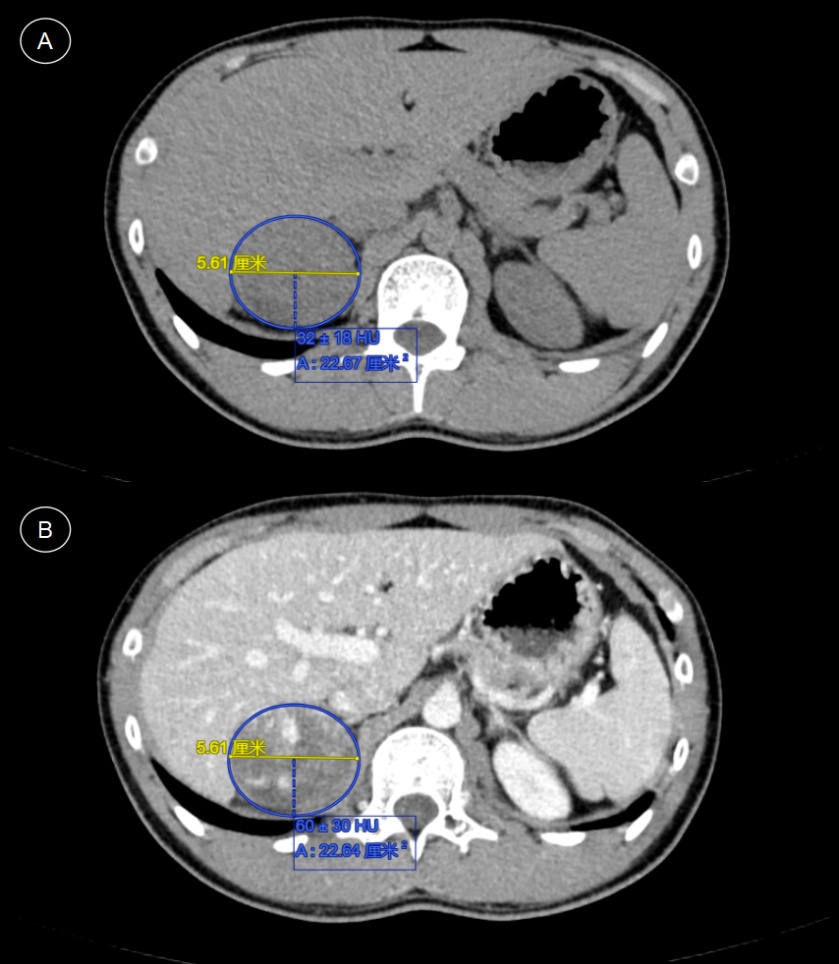

腹部CT平扫 + 增强:(见图1(A))右侧肾上腺区可见团块状软组织密度影,大小约55 mm × 51 mm,边界尚清晰,内部密度不均匀,平扫CT值约32 ± 18 HU;增强扫描(见图1(B))呈明显不均匀强化,CT值约60 ± 30 HU。双肾及左侧肾上腺未见明显异常,腹膜后及盆腔未见明显肿大淋巴结。影像学诊断考虑:右侧肾上腺意外瘤,恶性可能?

注:(A) CT平扫示右侧肾上腺区可见团块状软组织密度影,边界尚清,密度不均匀,CT值约32 ± 18 HU,大小约55 mm × 51 mm;(B) 增强扫描示肿块呈明显不均匀强化,CT值约60 ± 30 HU。

Figure 1. CT imaging features of the right adrenal mass

1. 右侧肾上腺肿块的CT影像表现